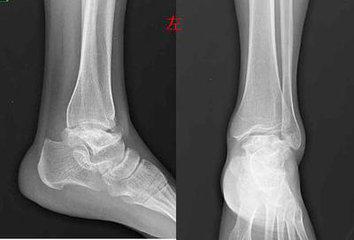

(图:孙先生的左足踝关节溃破严重)

(图:治疗后的左足踝关节X光)

查体:全身多关节处形成大小不等痛风石,双肘关节红肿,伴有刺痛感,双膝关节红肿疼痛,无法屈伸,左足踝关节痛风石溃烂,有明显异味。

实验室检查:疼痛视觉模拟评分(VAS)8~9分,尿酸717 μmol/L,肌酐218 μmol/L,C反应蛋白(CRP) 25mg/L。

经过第三个疗程治疗,孙先生的全身多关节痛风石全部溶解,没有僵硬感,左足踝关节溃烂处基本恢复正常,各个关节活动无阻。